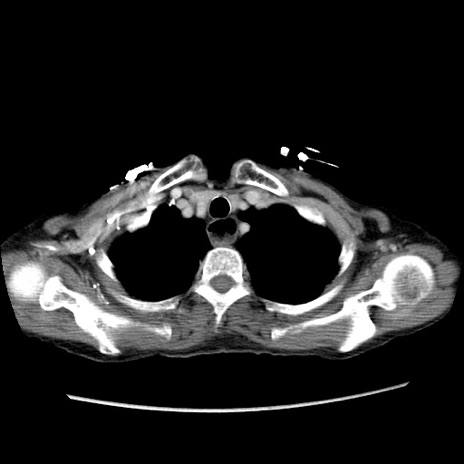

症例25(横断像)

【症例】80歳代女性

【主訴】胸のつかえ感

【現病歴】約9時間前に食後から胸のつかえた感じあり、嘔吐あり、来院。

【既往歴】胃癌(全摘)、胆摘、虫垂炎

【身体所見】心窩部に圧痛あり、反跳痛なし。

【データ】WBC 5700、CRP 0.05